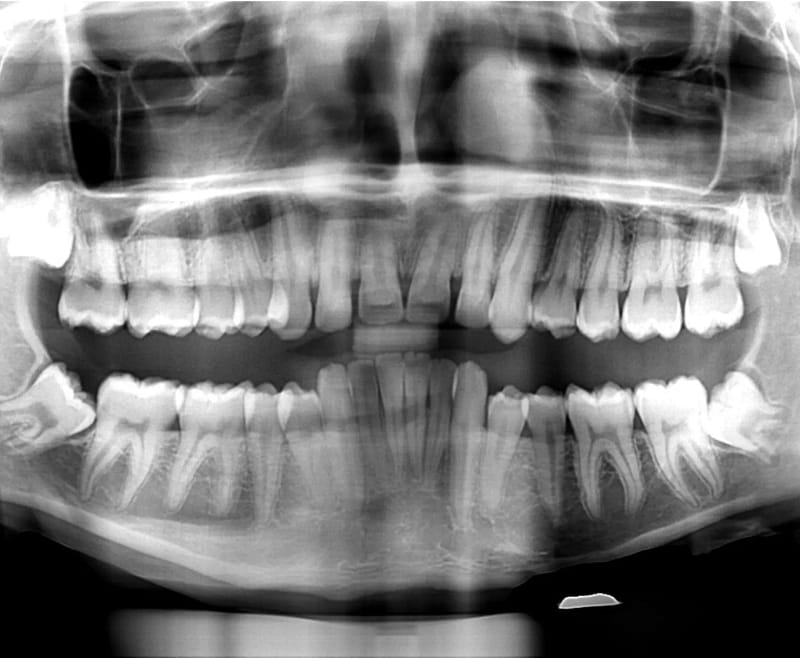

En Estudio Rx, entendemos la importancia de una evaluación dental precisa y completa. Es por eso que ofrecemos Radiografía Panorámica, un servicio esencial para un diagnóstico detallado de tu salud bucal. Este tipo de radiografía captura una imagen amplia de toda tu boca en una sola toma, mostrando todos los dientes, mandíbulas, y estructuras circundantes, desde las raíces hasta los huesos, de manera clara y detallada.

La radiografía panorámica es fundamental para detectar problemas como caries, fracturas, dientes retenidos, y patologías en las mandíbulas que pueden no ser visibles en una revisión convencional. Además, es una herramienta indispensable para planificar tratamientos complejos, como implantes dentales, ortodoncia y cirugías maxilofaciales, permitiendo que los especialistas tengan una visión completa de tu situación bucal.